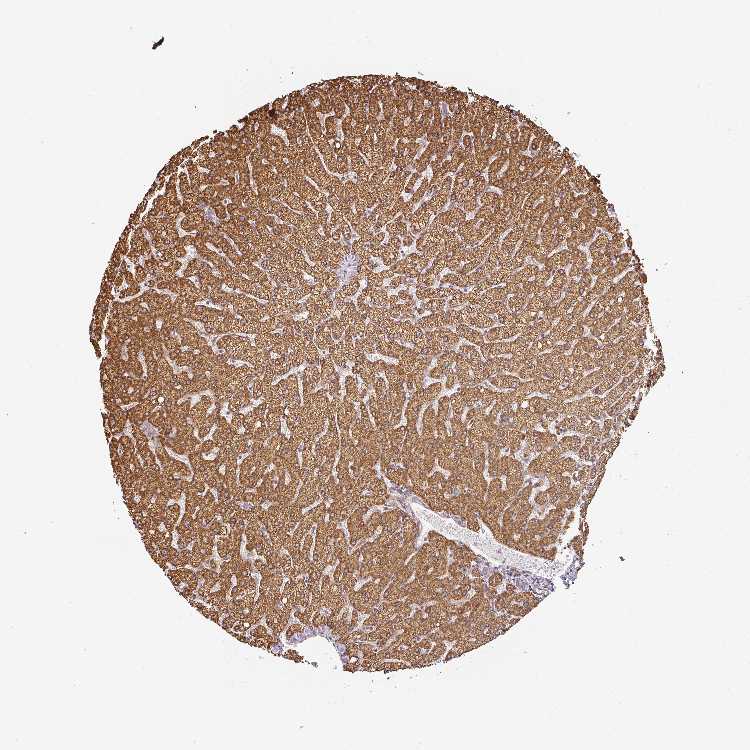

CNOT1